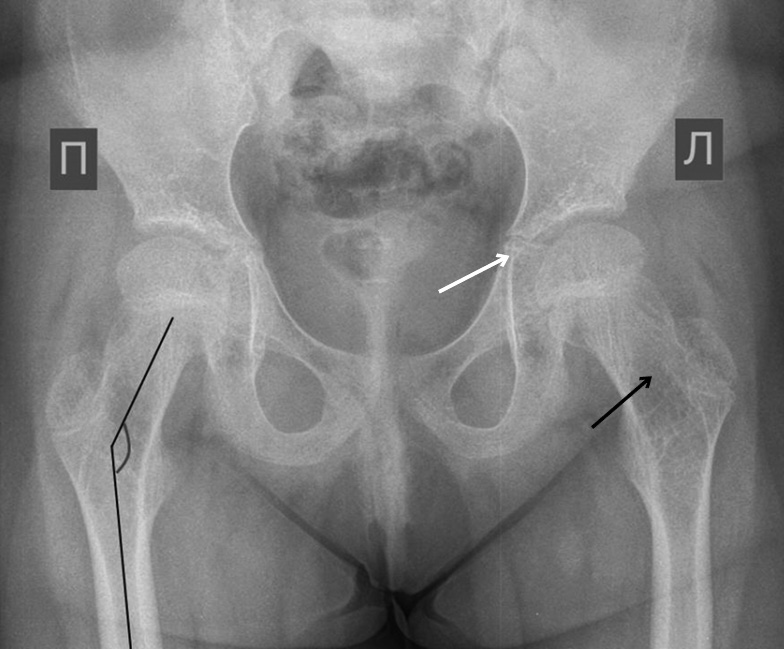

Radiography of patient 2’s hip joints revealed an increase in the neck–diaphyseal angle, decreased BMD, and disordered bone architecture of the proximal femur. Additionally, thinning of the bottom and protrusion of the acetabulum were observed (Fig. 5).

Fig. 5. Radiograph of the hip joints in direct projection in patient 2: increased neck–diaphyseal angle (black line), decreased mineral density, and disrupted bone architecture of the proximal femur (black arrow); thinning of the floor and acetabular protrusion (white arrow)